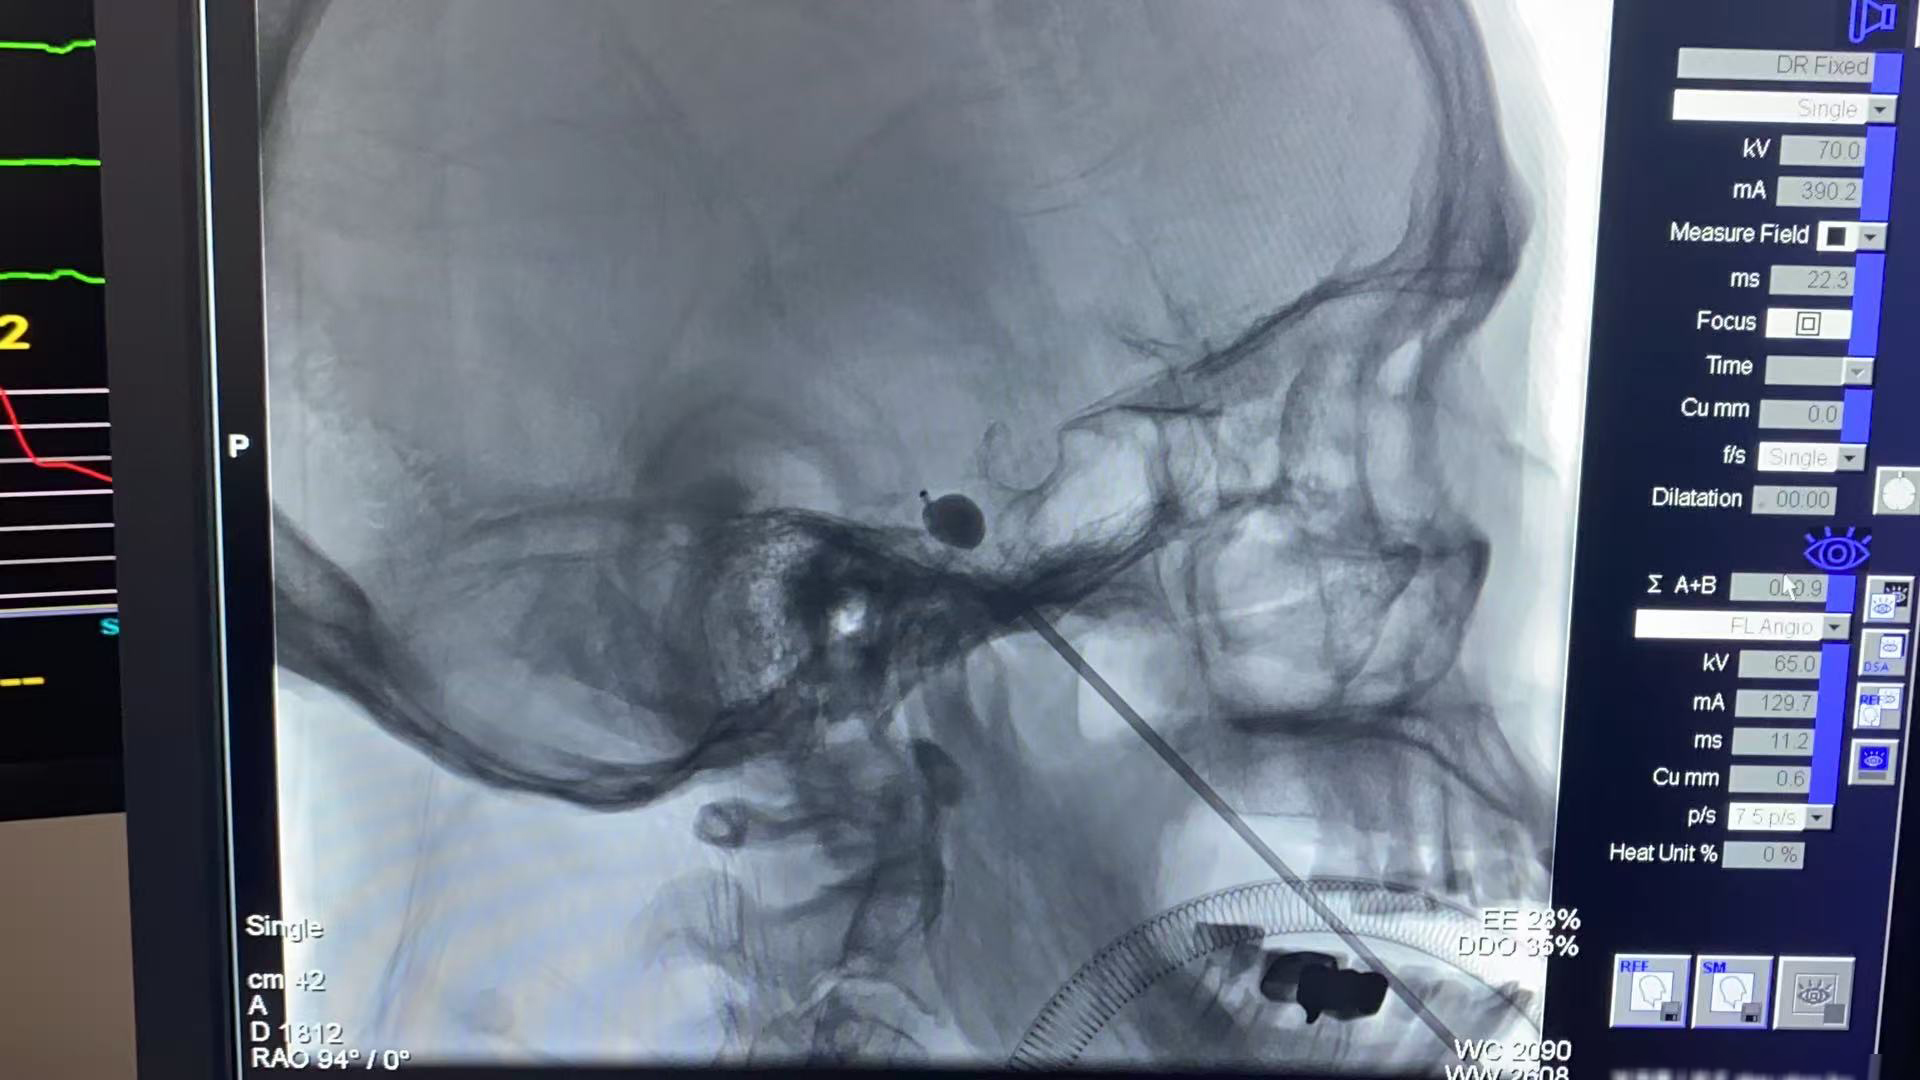

手术当日,神经外科团队精准穿刺定位,将球囊植入患者三叉神经半月节区域,整个过程仅50分钟。术中球囊位置良好,压迫过程平稳可控,患者生命体征平稳。术后,患者右侧面部疼痛基本消失,仅偶有轻微面部麻木感,恢复效果显著,复查头颅CT未见明显异常。